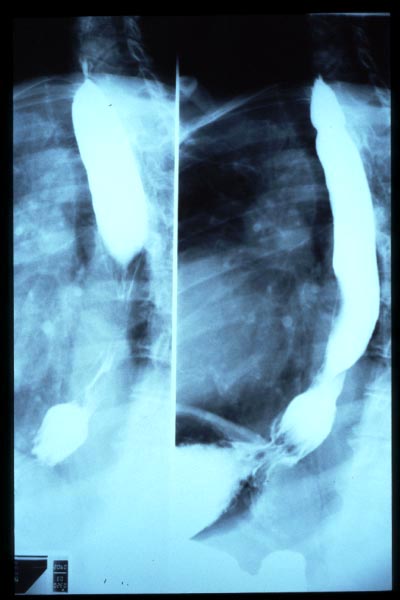

Hernia de hiato por deslizamiento al TGED.

Hernia de hiato por deslizamiento al TEGD.